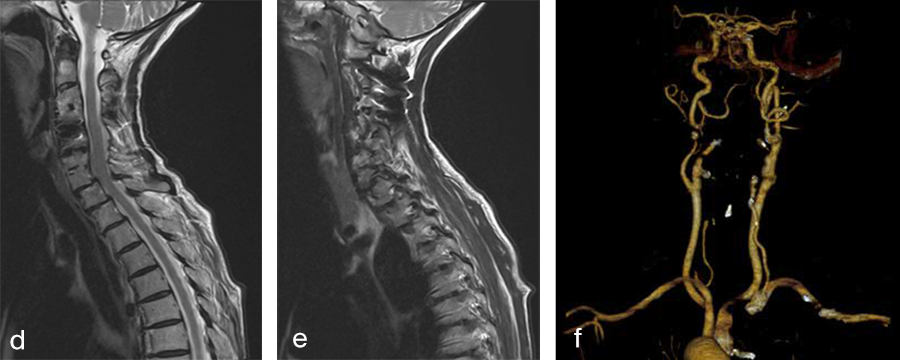

Her preoperative radiographic evaluation comprised two standard plane radiographs, functional radiographs, computed tomographic and magnetic resonance imaging scans (Fig 2) demonstrated:

- A fusion of the motion segments C2/3/4 and C6/7

- A moderate implant loosening of the posterior C2 screw on the right side

- An afunctional disc prosthesis at the level C4/C5 with significant heterotopic ossifications (grade III) accompanied by a facet joint osteoarthritis in this motion segment

- A nonunion at the level C5/C6 with residual mobility in this motion segment

- A highly mobile degenerative spondylolisthesis at the level C7/Th1 with bilateral neuroforaminal stenosis

Fig 2a–f Preoperative imaging showing: C2-C4 posterior instrumentation and fusion, anterior fusion after anterior cervical decompression and fusion (ACDF) C3/4 and C6/7, status after total disc replacement of C4/5 with heterotopic ossifications, nonunion C5/6 after ACDF C5/6, spondylolisthesis C7/Th1 with neuroforaminal stenosis on both sides and a normal cervical angiogram (cave: artefacts).